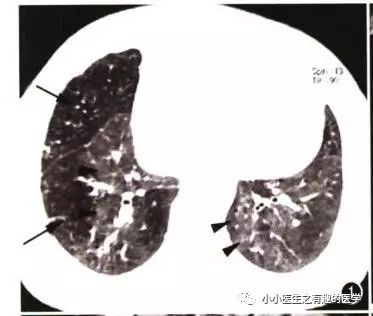

另外,CT发现肺纹理减少,也要警惕肺栓塞。先来说说马赛克。

马赛克征象:由于气道疾病或肺血管性疾病,引起相邻的肺区血液灌注上的差别而出现的不均匀肺密度区,称马赛克灌注。

以图说话,下面都是马赛克,关注了

如图:

假如CT平扫发现肺部某些地方血管稀疏,灌注不足,千万不要以为没事,有时候,就是肺栓塞,需要警惕。

马赛克,需要警惕肺栓塞,它是肺栓塞的间接表现。并且,在临床中,间断会遇到这样的情况。